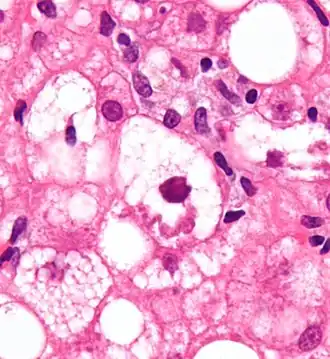

Mallory bodies are highly eosinophilic and thus appear pink on H&E stain. The bodies themselves are made up of intermediate cytokeratin 8/18 filament proteins that have been ubiquitinated, or bound by other proteins such as heat shock proteins, or p62/Sequestosome 1.[5]

Micrograph showing a Mallory body. Original magnification 400X. H&E stain. -